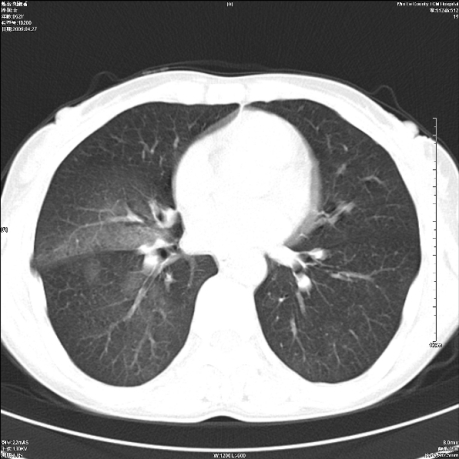

标题: CT19625:女52间断性喀血 [打印本页]

标题: CT19625:女52间断性喀血

考虑右肺下叶支气管病变,tb??

病灶内可见含气影。考虑右肺下叶内基底段炎症

右肺炎性改变,治疗后复查,或气管镜检查。

考虑右肺中叶感染性病变并右肺中、下叶肺泡积血;建议抗炎、止血治疗后复查。

右肺中叶炎症;右肺中、下叶肺泡积血

右肺中叶支气管扩张并感染或咳血沉积,块右肺中下叶肺泡积血。

右肺中叶慢性炎症伴局部支扩并中下叶肺泡积血。

考虑右肺中叶感染性病变并右肺中、下叶肺泡积血。建议治疗后复查。